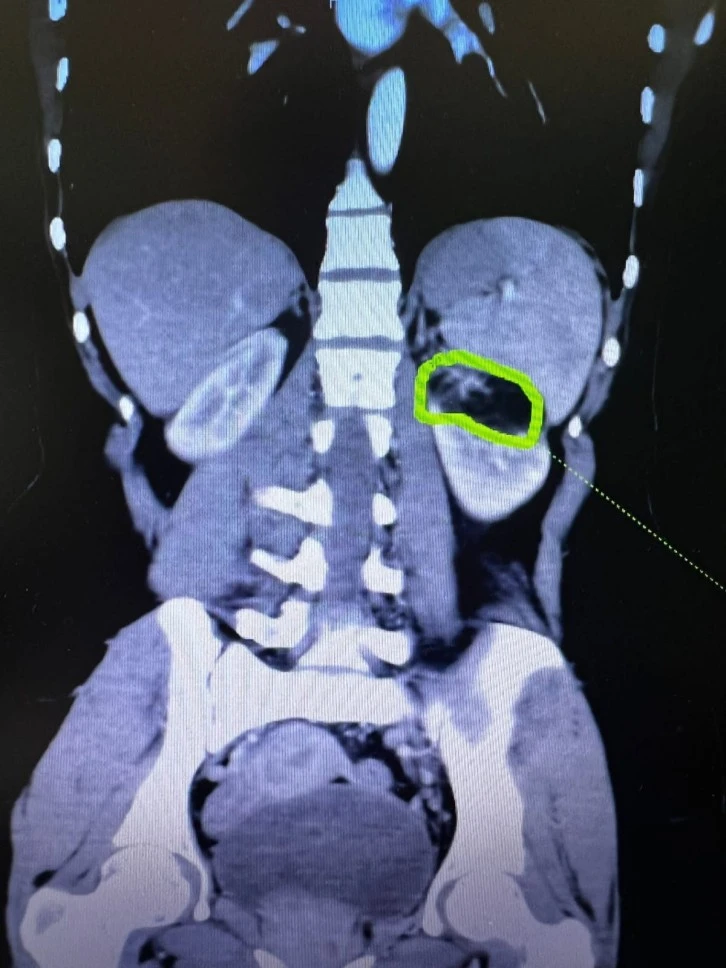

İlimizin köklü kurumlarından olan 25 Aralık Devlet Hastanesi, başarılı ameliyatlarına bir yenisini daha ekledi. Hastanemizde görev yapan Üroloji Uzmanı Op.Dr.Mehmet ÖZTÜRK tarafından 58 yaşındaki ileri derece obez olan hastanın, sağ böbreğindeki kitle nedeniyle, kitlenin yeri ve boyutunun riskli olmasına rağmen Parsiyel Nefrektomi Ameliyatı (böbrekten kanserli dokunun çıkarılması) (Böbrek Koruyucu Kanser Ameliyatı) başarıyla gerçekleştirildi.

Riskli vakalardan bir diğeri de sol böbrekteki 6 cm lik kitleye bağlı kanama olasılığından dolayı gebeliği sonlandırılmış E.S 'ye başarılı geçen operasyonla “Böbrek Koruyucu Kanser Ameliyatı" yapılarak böbreğe zarar vermeden kanserli doku çıkarılmıştır. Operasyon sonrası yapılan takiplerinde sağlık durumu iyi olan hasta 3. günü taburcu edilmiştir. Ayrıca bir diğer vakada 78 yaşındaki kadın hastaya, sol böbrekte 3 cm kitle nedeniyle “Sol Parsiyel Nefrektomi Ameliyatı” da ekibimiz tarafından başarılı bir şekilde uygulanmıştır.

Tümörün boyutu ve yerleşimi nedeniyle böbrek koruyucu cerrahi imkanı olmayan hastalara hastanemizde radikal nefrektomi (Tümör ile birlikte böbreğin tamamen çıkarılması) ameliyatı başarı ile gerçekleştirilmektedir.